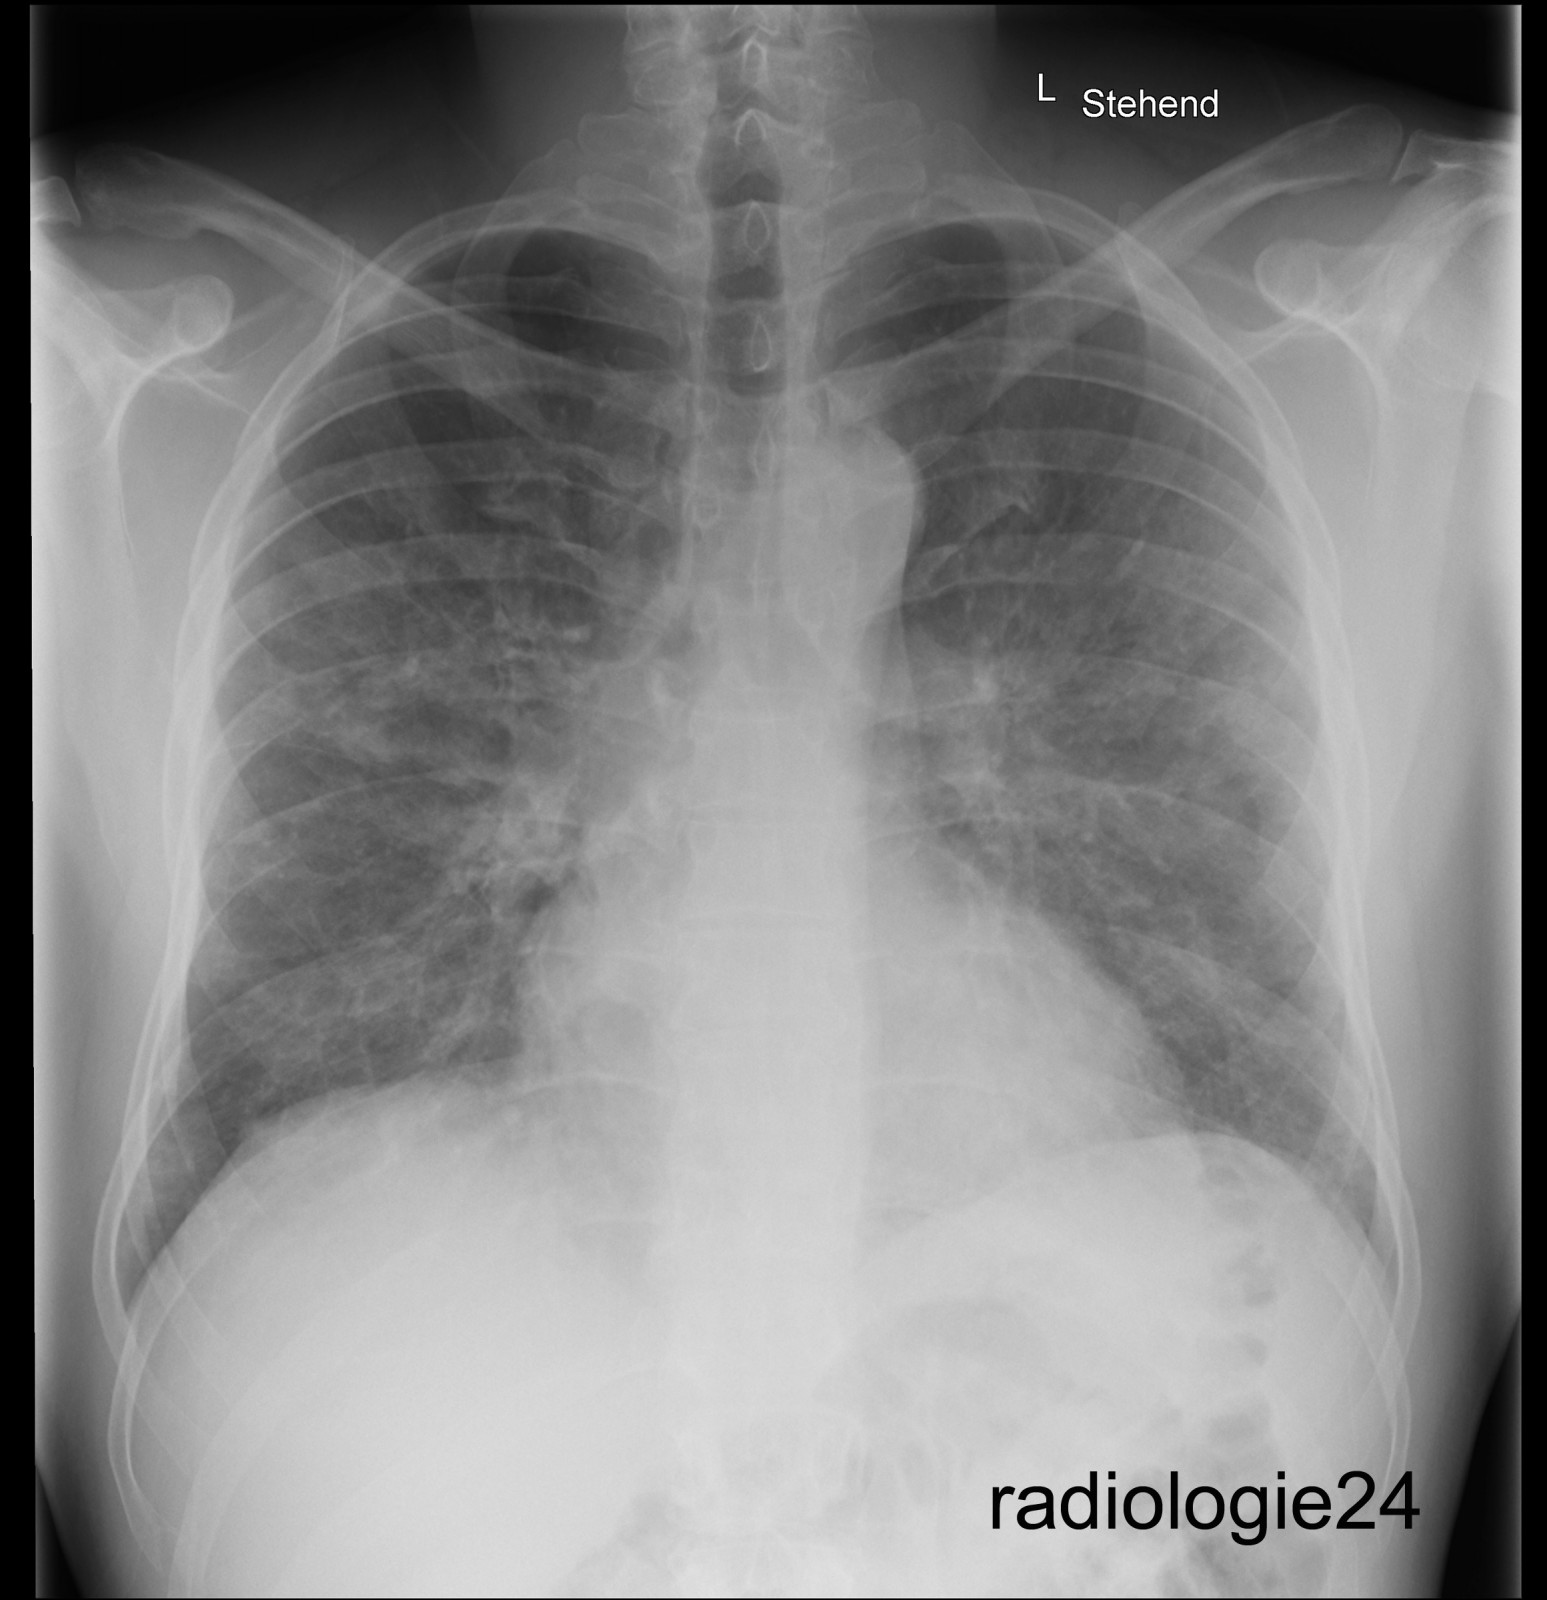

Röntgenfall des Monats August 2018 mit Auflösung

40 jähriger Patient

Triathlon Sportler.

Bei einem Wettkampf muss der Patient wegen akut auftretender Dyspnoe nach dem Schwimmen, die Disziplin des Fahrradfahrens abbrechen und kann den Triathlon nicht beenden.

Einlieferung in die Notaufnahme des nächstliegenden Spital.

Ihre Diagnose?

Weitere radiologische Diagnostik notwendig?